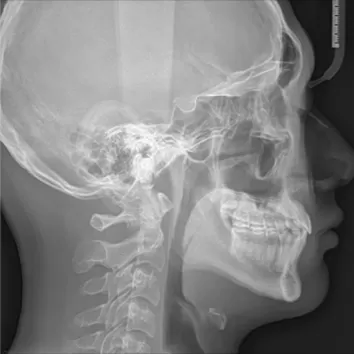

X-rays before treatment

[Panoramic Radiography/Lateral Cephalogram]